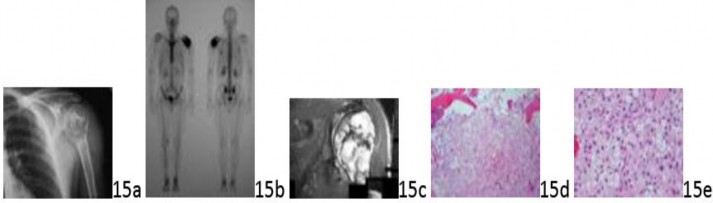

Question 15 A 28-year-old man has had left shoulder pain for 1 year. The pain is constant and has steadily worsened over time. History reveals that he underwent curettage for a "noncancerous bone tumor" 5 years ago. A radiograph, bone scan, MRI scan, and biopsy specimens are shown in Figures 15a through 15e. What is the most appropriate treatment for this patient?

Question 15 A 28-year-old man has had left shoulder pain for 1 year. The pain is constant and has steadily worsened over time. History reveals that he underwent curettage for a "noncancerous bone tumor" 5 years ago. A radiograph, bone scan, MRI scan, and biopsy specimens are shown in Figures 15a through 15e. What is the most appropriate treatment for this patient?

1. ## Wide resection alone

2. ## Resection and chemotherapy

3. ## Intralesional curettage and grafting

4. ## Forequarter amputation

5. ## Radiation therapy and prophylactic internal fixation

DISCUSSION: The radiographs and histology are consistent with a clear cell chondrosarcoma. The treatment is wide resection. No chemotherapy is indicated because this is a locally aggressive tumor with minimal risk of metastasis.

Intralesional curettage may be appropriate for a benign bone tumor but not for a clear cell chondrosarcoma. Amputation and radiation therapy are not indicated to achieve local disease control. This case illustrates the occasional problems with diagnosis of this tumor. The Preferred Response to Question # 15 is 1.

1. ## Wide resection alone

2. ## Resection and chemotherapy

3. ## Intralesional curettage and grafting

4. ## Forequarter amputation

5. ## Radiation therapy and prophylactic internal fixation

DISCUSSION: The radiographs and histology are consistent with a clear cell chondrosarcoma. The treatment is wide resection. No chemotherapy is indicated because this is a locally aggressive tumor with minimal risk of metastasis.

Intralesional curettage may be appropriate for a benign bone tumor but not for a clear cell chondrosarcoma. Amputation and radiation therapy are not indicated to achieve local disease control. This case illustrates the occasional problems with diagnosis of this tumor. The Preferred Response to Question # 15 is 1.